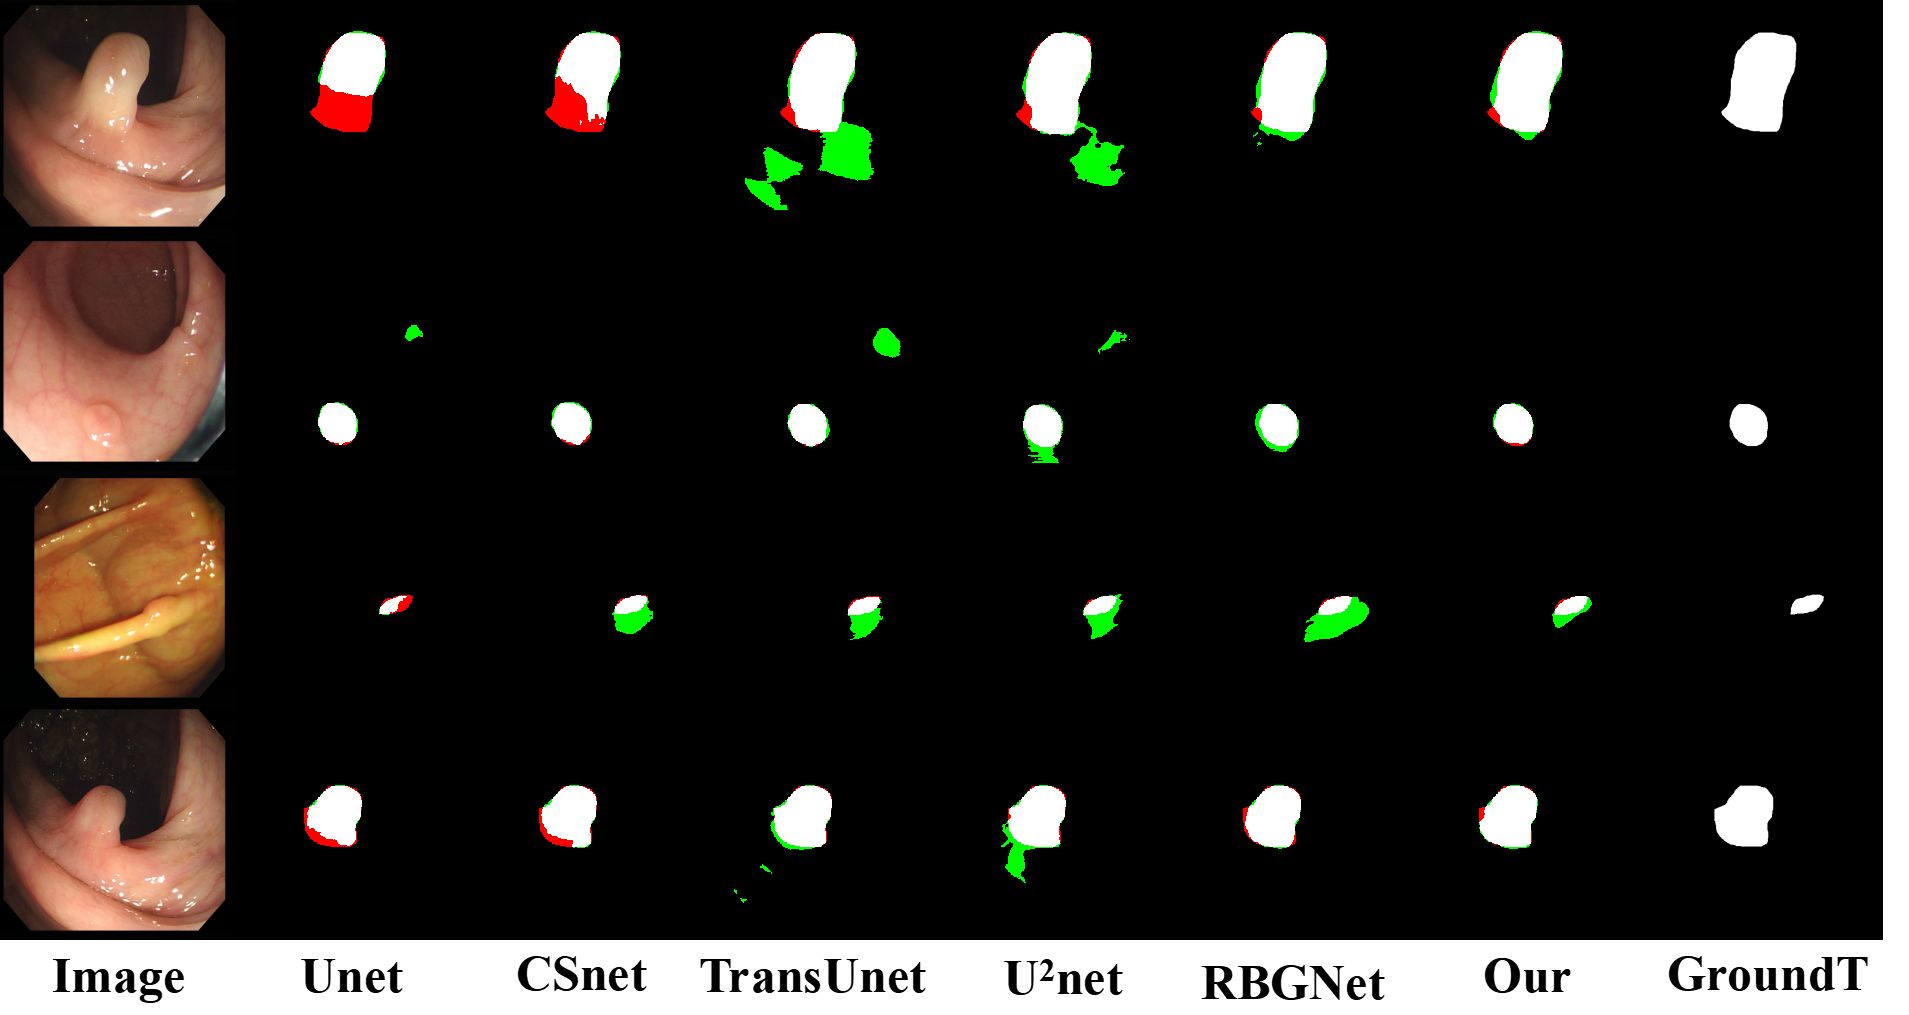

Figure 14: Comparison of polyp segmentation results. red indicates under-segmentation and green indicates over-segmentation.

To comprehensively evaluate the generalization capability of MTG-Net, we performed extended validation on the benchmark CVC-300 dataset provided by the institution  [56], which is used for polyp detection and segmentation in colonoscopy images. The quantitative results, as shown in Table XI, show that our MTG-Net obtains a Dice score of 89% and an IoU of 84%, both achieving the best performance across all comparisons. The qualitative results, illustrated in Fig. 14, further illustrating that MTG-Net is able to accurately delineate polyp boundaries and achieve precise lesion segmentation performance, particularly when handling polyp data with blurry boundaries. This indicates the potential of using MTG-Net for a wide range of applications.